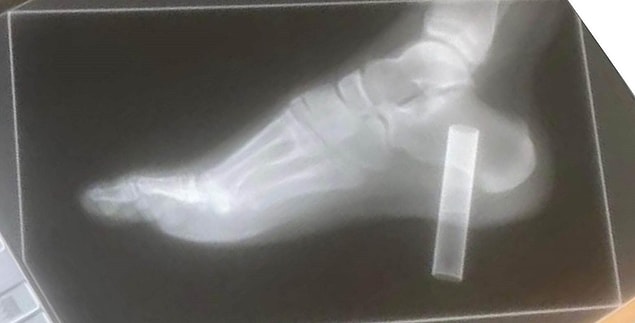

Ancak yaklaşık 10 santimetrelik cihaz, 13 yaşındaki çocuğun spor ayakkabısı ve çorabını delerek ayağına saplandı.

Annesi Samantha Robinson ile alelacele Cirencester Hastanesi’ne giden Bennett, durumunun kritik olması nedeniyle Gloucester Kraliyet Hastanesi'ndeki acil servise nakledildi ve elektronik sigaranın talihsiz çocuğun topuk kemiğine kadar girdiği ortaya çıktı.

Çünkü iki hafta sonra kontrol amaçlı gidilen muayenede doktorlar, Bennett’ın kırık topuk kemiğindeki bir enfeksiyon nedeniyle ayağının kesilme olasılığının yüksek olduğunu söylemiş.